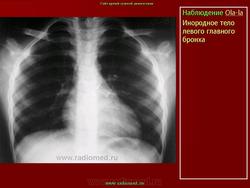

Инородные тела.